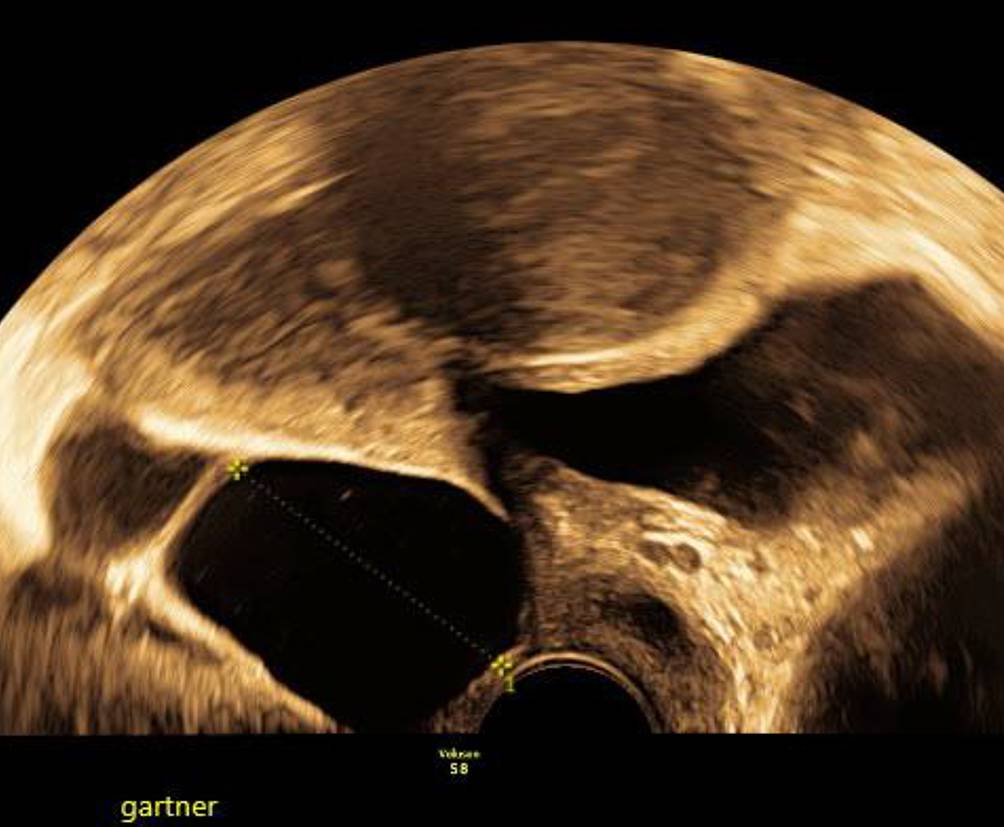

Abb. 5

Mit dem Abdominalschallkopf von perineal geschallte, seit 4 Jahren konstante Gartner-Gang-Zyste im Bereich des Fornix vaginae

Bild vergrößern

Abb. 6

Über Jahre konstante Gartner-Gang-Zyste, die trotz der unmittelbaren Nähe zur Blase der Patientin nie Beschwerden machte

Die Gartner-Gang-Zyste

Gartner-Gang-Zysten sind im Prinzip harmlos, das Innere der Zysten ist meist dünnflüssig, kann aber auch gallertartige Konsistenz haben [4]. Selten – und dann eher im jugendlichen Alter – können sie sehr groß werden [5]. Es gibt einzelne Fallberichte von malignen Prozessen im Vaginalbereich, die aus Gartner-Gang-Zysten entstanden sein sollen [6, 7]. Beobachten mittels Bildgebung ist bei symptomlosen Patientinnen einer Punktion oder Exzision auf jeden Fall vorzuziehen (Abb. 5 und 6).